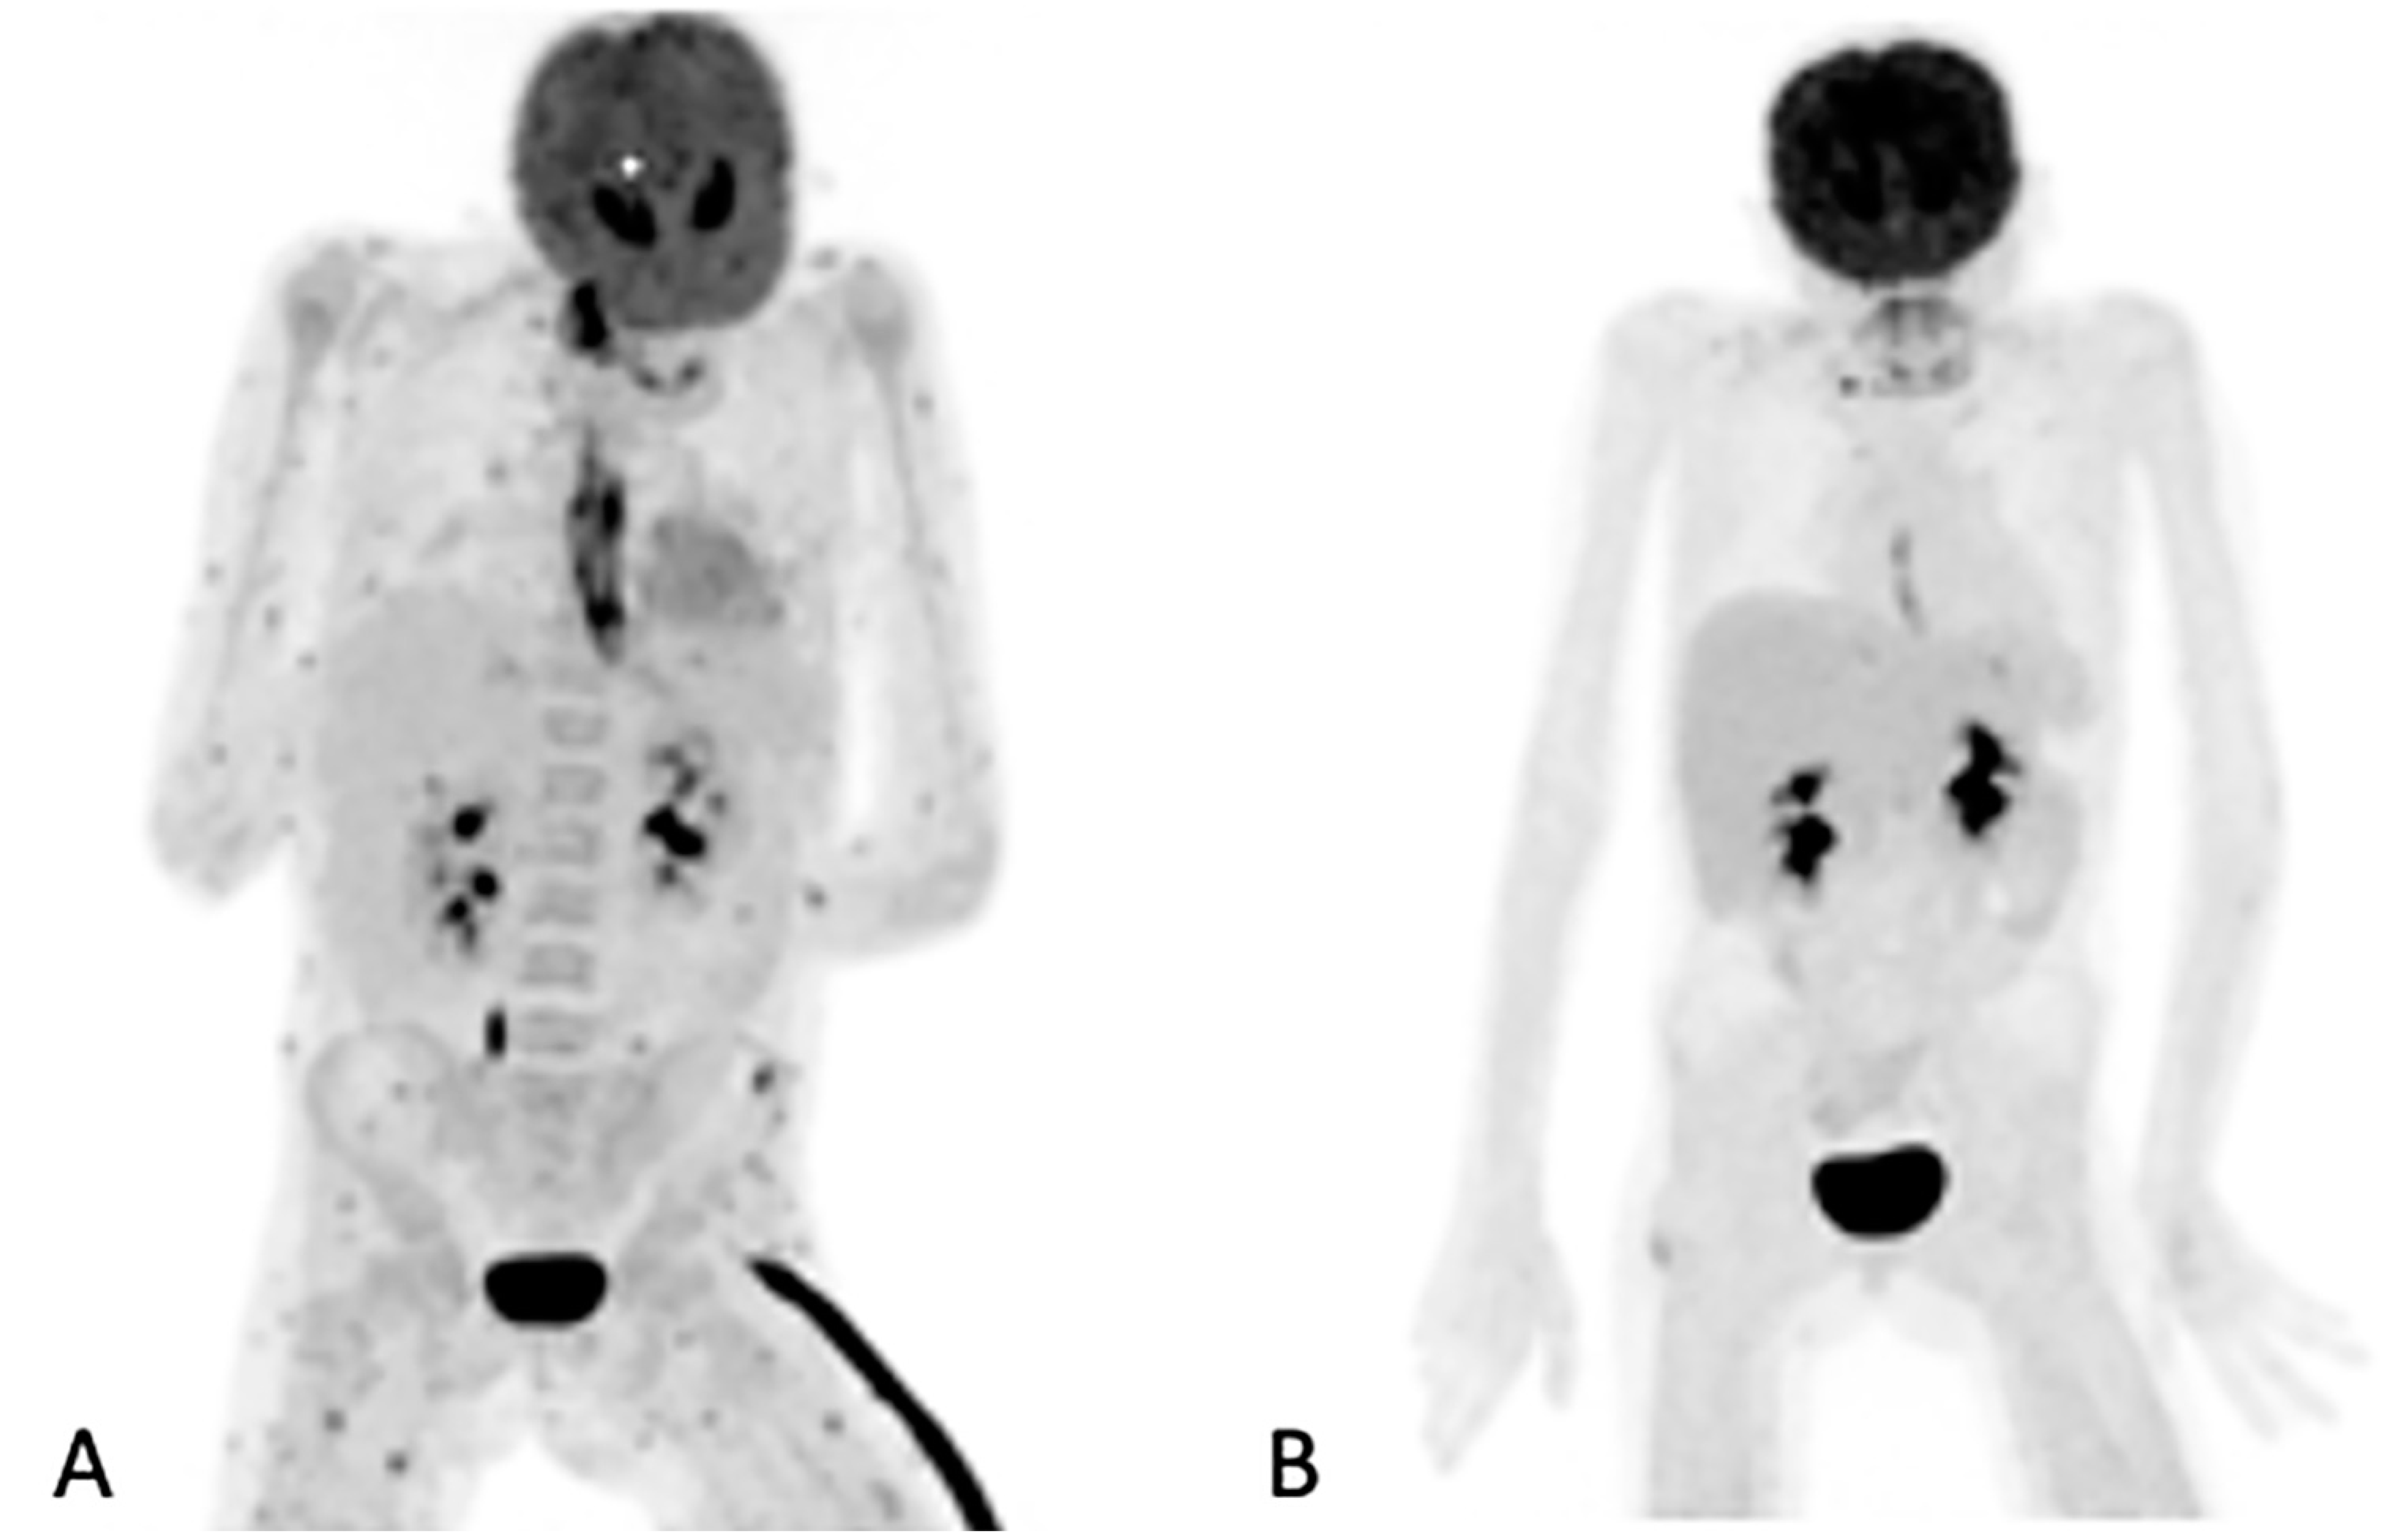

3.5. Added Value Due to the Metabolic Assessment of Lesions by Patient

Figure 3. Ten-year-old female with acute myeloid lymphoma who developed a fever, on chemotherapy, with no response to antibiotics. An abdominal ultrasound demonstrated bilaterally enlarged kidneys. Initial [18F]FDG PET/CT MIP image (A) showed focal metabolic uptake in kidneys, spleen and esophagus. She was started on antifungal treatment, but the fever persisted, and a repeat study (B) showed the worsening of renal splenic lesions with no pulmonary lesions. The antifungal treatment was changed; the fever subsided, and the serum infective markers decreased. A repeat [18F]FDG PET/CT performed after 6 weeks (C) showed resolution of the pulmonary and most of the renal and splenic lesions. The treatment was continued for another month, and a follow-up [18F]FDG PET/CT (D) showed a complete metabolic response that helped the clinician to end the antifungal treatment.